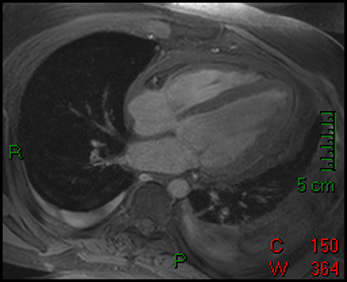

18) This image is most consistent with what diagnosis?